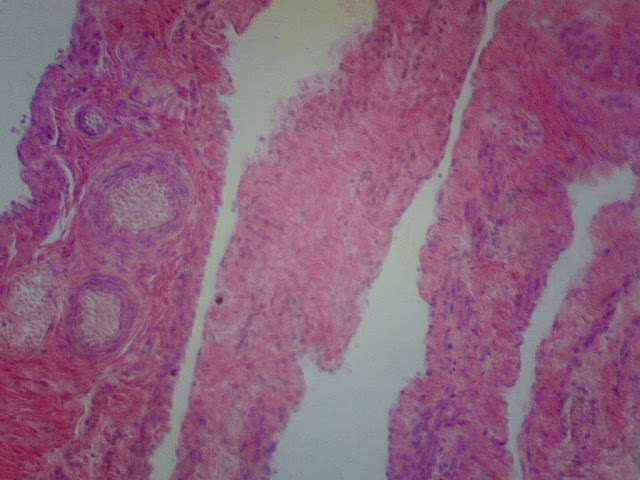

Яєчник